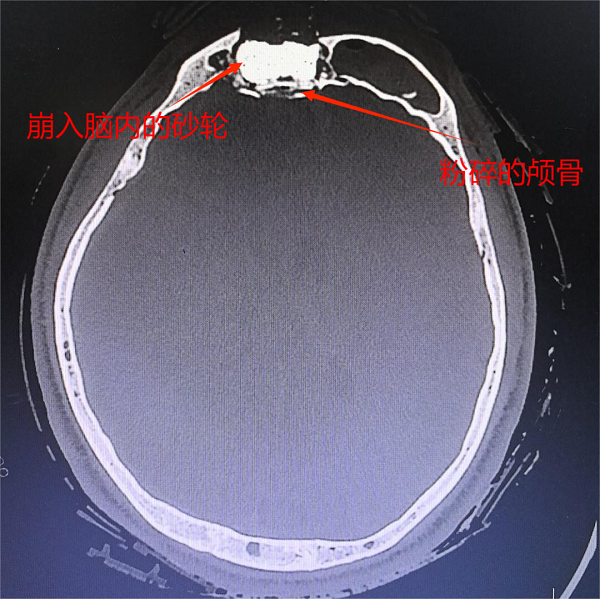

金秋九月,刚刚结束高考的19岁少年刘小刚(化名)在工地上遭遇事故,因高速旋转的磨砂轮突然崩裂,锋利碎片瞬间击穿其头皮,深深嵌入颅内。工友们第一时间将他送往陕西中医药大学第二附属医院,一场与死神赛跑的生命救援就此展开。

见状,医院立即启动急诊绿色通道。急诊团队迅速为小刘包扎止血、稳定生命体征,同时紧急联系神经外科。

“必须立即手术!”医院医务人员在安抚家属、详细沟通方案的同时,火速组织团队准备手术。手术麻醉科全程保障生命体征稳定。手术顺利完成后,小刘转入重症医学科,在严密监护下逐步脱离生命危险。